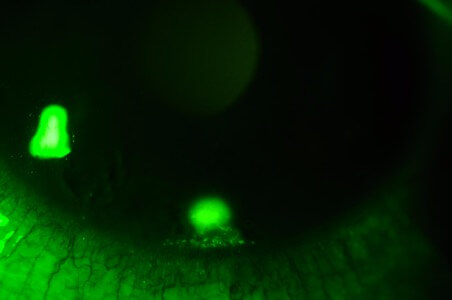

血管擴張

照片由香港理工大學眼科視光學院提供